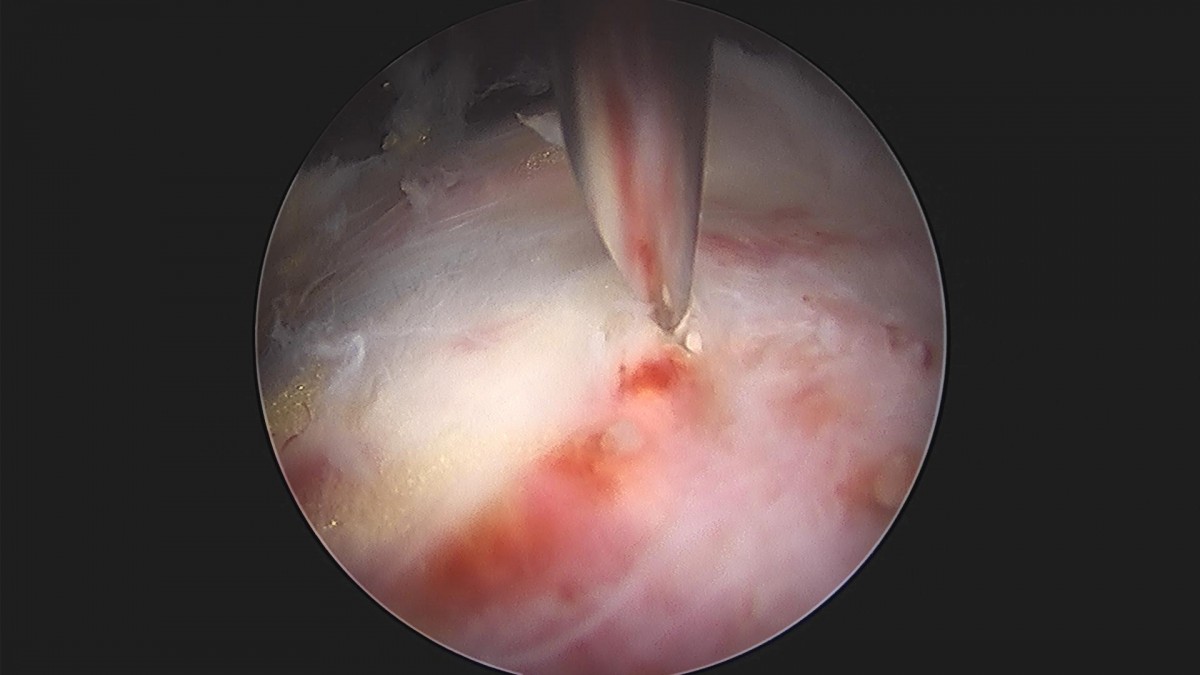

이재상원장님 어깨 견봉하 감압술 박미O 환자

작성자 최고관리자 댓글 0건 조회 1,297회 작성일 22-11-01 15:24